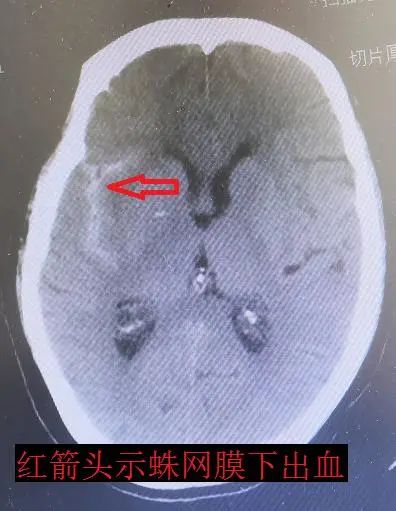

刘阿姨已经67岁了,既往身体比较健康,突然出现剧烈头痛,随后出现恶心呕吐,在家中休息后不见好转,家属立即送至我院,此时,距离发病仅仅过去两小时,我院急诊接诊后立即进行头CT检查,结果显示蛛网膜下腔出血。根据CT影像表现高度怀疑颅内动脉瘤。

神经外科二组主任王宝庆带领副主任医师郭知伟和住院医师王尧迅速为患者做了脑血管造影,DSA检查结果显示:颅内动脉瘤(右侧颈内动脉交通段动脉瘤,与头部CT显示出血吻合)。病因明确了,动脉瘤破裂出血是本次发病的罪魁祸首。但是患者脑部血管为典型的“三型弓”,介入治疗动脉瘤导管到位十分困难,但考虑到脑动脉瘤的危害,如果第二次破裂出血的死亡率达到50%以上,患者将随时面临死亡的危险,会引起脑积水、脑出血等并发症。王宝庆主任根据病人特点与患者家属充分沟通,建议手术治疗,言简意赅地介绍了介入和开刀两种手术方式的利弊,最终家属选择开颅夹闭动脉瘤。